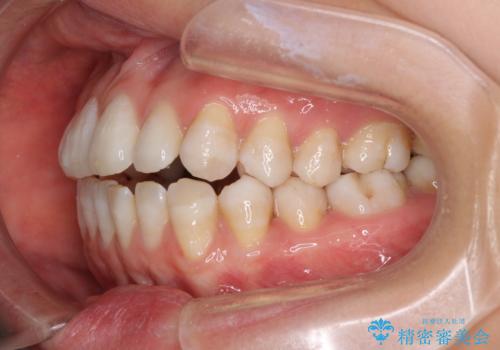

話しにくいオープンバイト インビザラインによる矯正治療

- 前歯の上下スペースによる話しにくさを気にして来院された患者様です。

インビザラインにより上下の前歯の隙間を閉じていくこととしました。

上下の奥歯を圧下させるようにすることで、前歯を接触させるように計画しました。

隙間に舌が入り込むことが話しにくさに繋がっていたため、舌の筋肉のトレーニングも並行して行い、話しにくさの改善と後戻りの抑制を図りました。